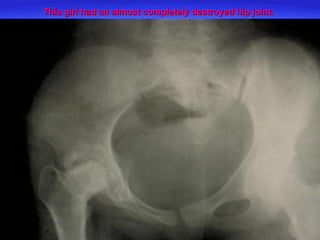

This girl had an almost completely destroyed hip joint.